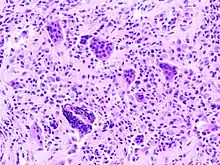

| Micrograph of diffuse TGCT, also known as pigmented villonodular synovitis. H&E stain. | |